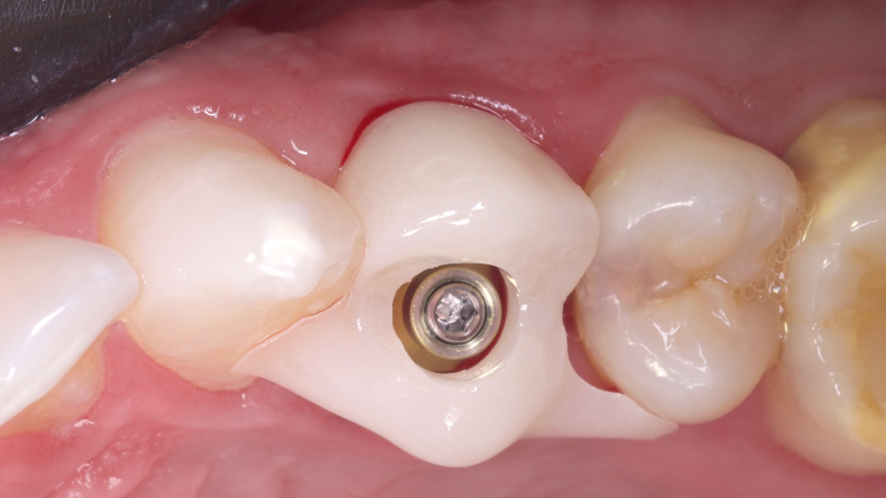

Após a exodontia foi posicionado o guia cirúrgico impresso e iniciou-se o protocolo de fresagem do kit cirúrgico Implaguide da Implacil De Bortoli: fresa lança 2,0, seguida pela fresa 3,5×13, buscando subfresagem para maior estabilidade primária. O implante dentário instalado foi o Maestro de 4x13mm (Implacil De Bortoli). Foi realizado em seguida a instalação do pilar Ideale 4,5 x 4 x 2,5 mm e a coifa parafusada do pilar Ideale 4,5x4mm.

Em seguida foi realizado a captura do provisório em PMMA na coifa de titânio com resina fluida e após acréscimos, acabamento e polimento fora da boca, o provisório foi aparafusado e a cirurgia foi finalizada sem a necessidade de sutura.

Após o período de seis meses de acanhamento clínico foi realizado a confecção da coroa definitiva. Tendo como passo inicial a remoção da coroa provisória feita de PMMA, sobre o qual foi observado um excelente perfil de emergência, e realizado o escaneamento da região com o transfer digital do pilar Ideale de 4,5x4mm, e escaneamento do provisório, o laboratório confeccionou uma coroa definitiva de zircônia monolítica baseada no perfil de emergência do provisório escaneado e o conjunto foi levado a boca e aparafusado com parafuso Torx (Implacil De Bortoli).